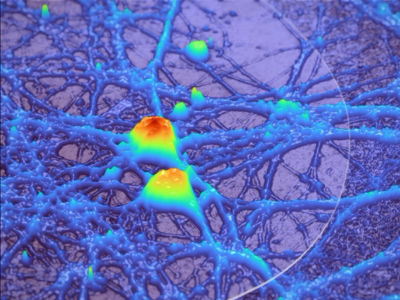

No 18 | Lever le voile sur la connectivité neuronale à l’aide de l’holographie